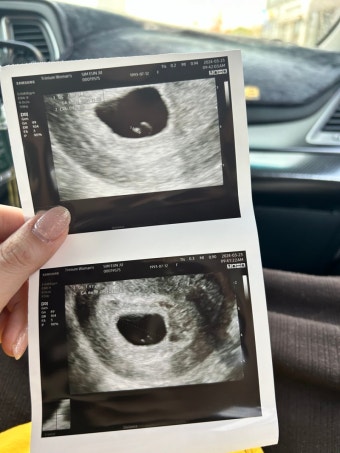

임신 5주차는 본격적으로 임신 여부를 확인하고 병원을 방문해야 하는 시기입니다. 가정용 임신 테스트기에서 양성이 나왔다면, 산부인과를 방문해 정확한 진단을 받아야 합니다. 혈액 검사와 초음파 검사를 통해 자궁 내에 정상적으로 착상되었는지 확인할 수 있습니다.

이 시기에 병원을 방문하면 태아의 위치, 착상 여부, 다태아 여부 등을 확인할 수 있고, 임신 유지에 필요한 초기 상담과 검진을 받을 수 있습니다. 특히 자궁외 임신이나 유산의 위험을 조기에 발견할 수 있기 때문에, 병원 방문은 절대 미루지 말아야 합니다.

5주차의 태아는 아직 매우 작으며 약 1.5~2mm 정도입니다. 이 시기에는 신경관이 형성되며, 뇌와 척수가 점차 구체적인 형태를 갖추게 됩니다. 심장 역시 이 시기부터 박동을 시작하며, 초음파를 통해 심박동이 관찰될 수도 있습니다. 비록 눈에 띄는 외형은 없지만, 태아의 주요 기관들이 형성되는 시기이므로 영양 섭취와 생활습관에 신경 써야 할 중요한 시기입니다.